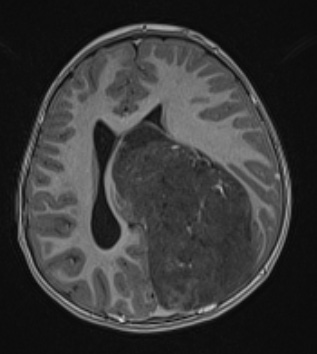

Washington University Experience | NEOPLASMS (EMBRYONAL) | ETMR - Embryonal Tumor Multilayered Rosettes | 1A4 ETMR (NP20-592) T1w axial - Copy

Administration of contrast fails to show substantial enhancement in a T1-weighted contrast administered scan.